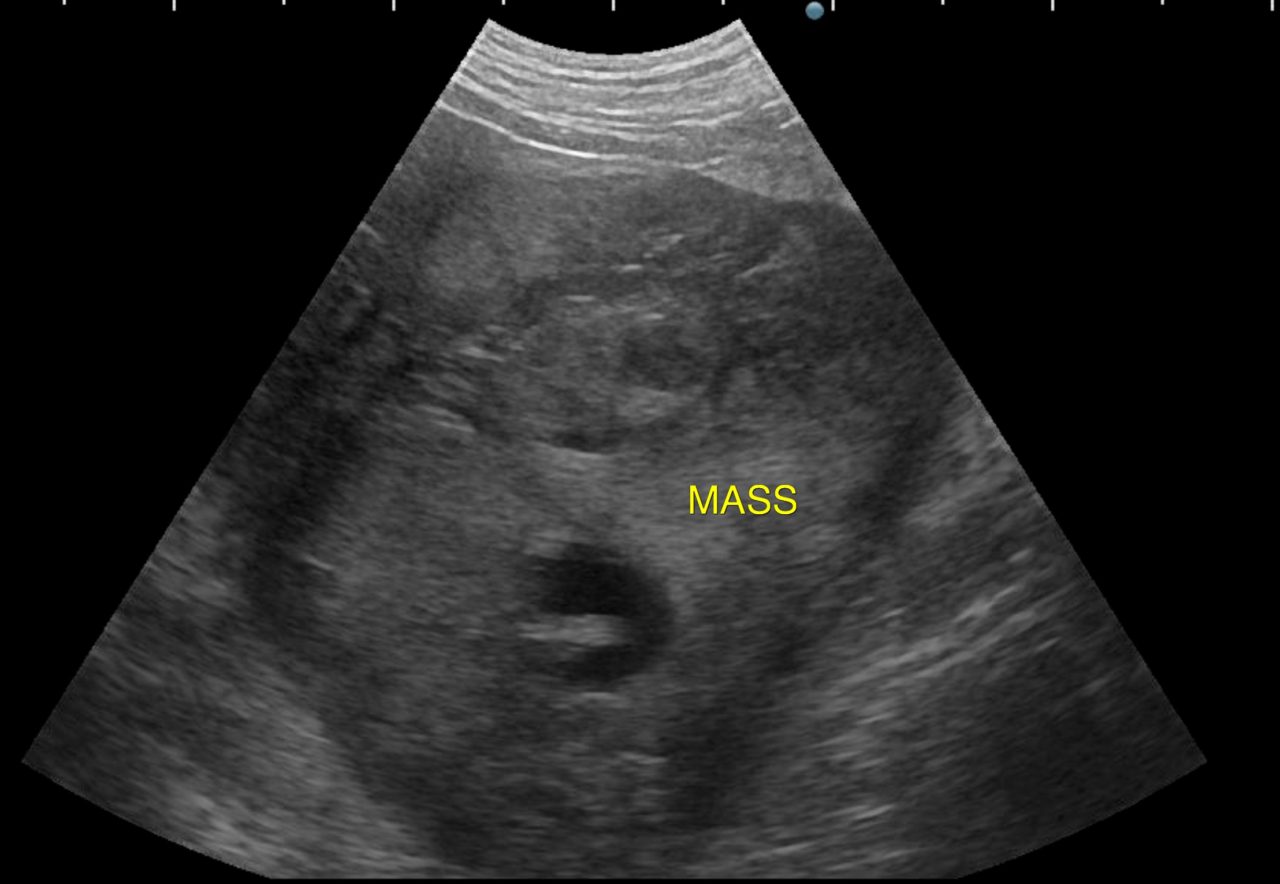

歯茎白い。すぐさま腹部の超音波検査をして”腹腔内液体貯留と腹腔内腫瘤を確認”

エコーでは脾臓と肝臓にMASSを確認。

開腹すると脾臓と肝臓に腫瘤病変があり破裂、出血していました。